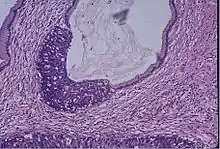

Cervical screening by the Pap test or other methods is highly effective at detecting and preventing cervical cancer, although there is a serious risk of overtreatment in young women up to the age of 20 or beyond, who are prone to have many abnormal cells which clear up naturally.[13] There is a considerable range in the recommended age at which to begin screening around the world. According to the 2010 European guidelines for cervical cancer screening, the age at which to commence screening ranges between 20–30 years of age, "but preferentially not before age 25 or 30 years", depending on the burden of the disease in the population and the available resources.[14]